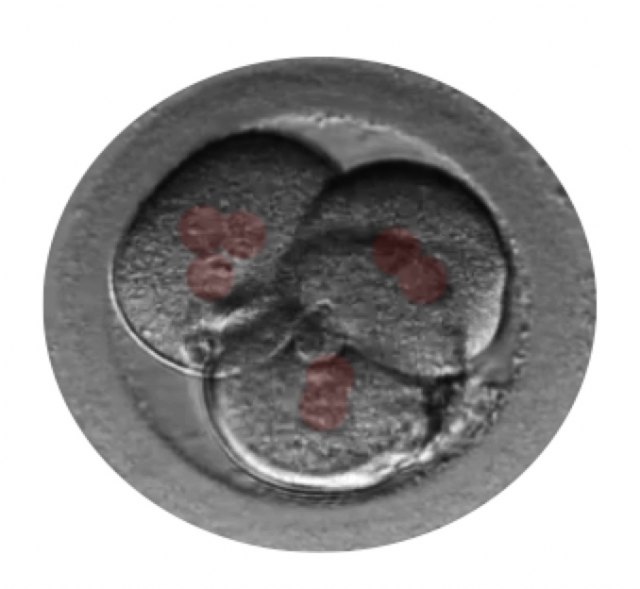

El Dr. Borja Marquès es el autor del estudio "Signos de auto-reparación de los embriones en el laboratorio de FIV" cuyas conclusiones apuntan que los embriones poseen un mecanismo de auto-corrección ignorado hasta hoy. Según este trabajo que se presenta esta semana en Murcia, en el 36° Congreso de la Sociedad Española de Ginecología (SEGO), embriones que han sufrido división reversa (desaparición de alguna de sus células) o multinucleación (presencia de dos o más núcleos en alguna de sus células) pueden dar lugar a un embarazo normal y al nacimiento de un bebé sano.

Gracias a los incubadores con cámaras time-lapse (Embryoscope), en los laboratorios de Institut Marquès ha sido posible captar las imágenes de embriones con división reversa reabsorbiendo sus propias células y de embriones multinucleados expulsando las células anómalas en el 4° o 5° día de vida. Para conseguirlo, se ha analizado el desarrollo de 21.274 embriones, desde su fecundación hasta que llegaron a blastocisto.